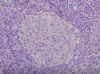

Non caseating granuloma.